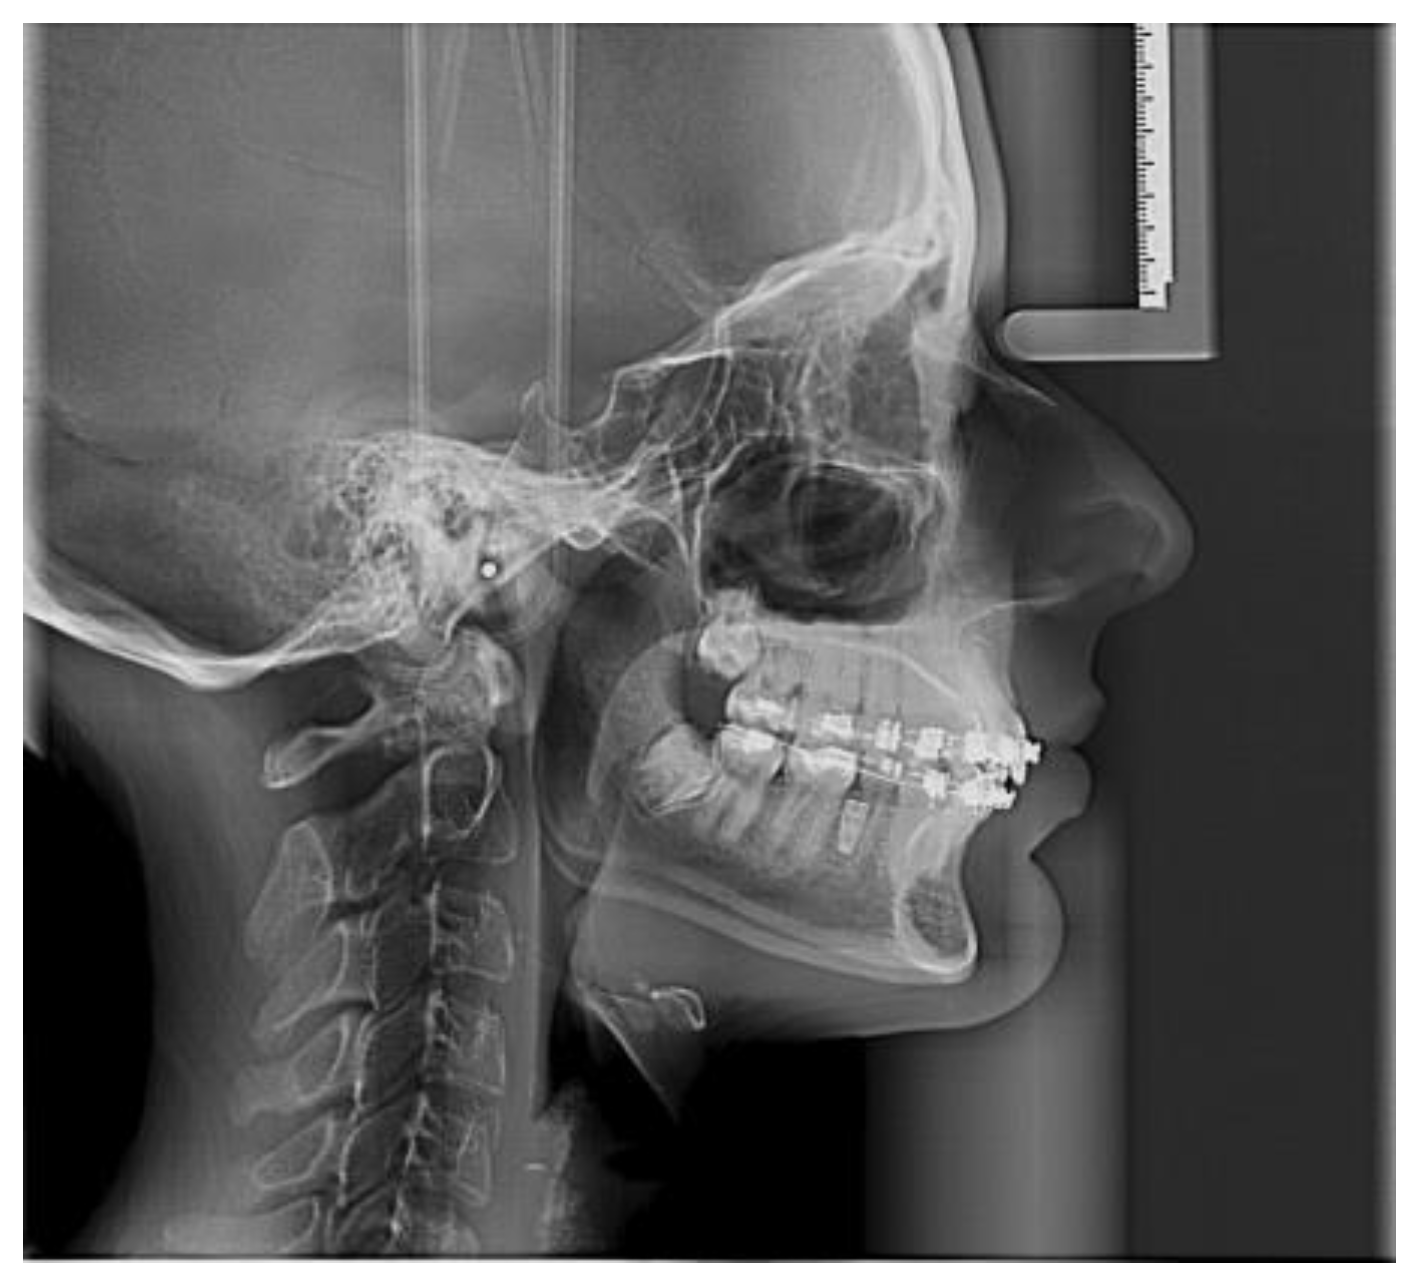

- Angle formed by the long axis of the incisor and the palatine plane—CP angle.

- Angle formed by the long axis of the incisive canal and the palatine plane—IP angle.